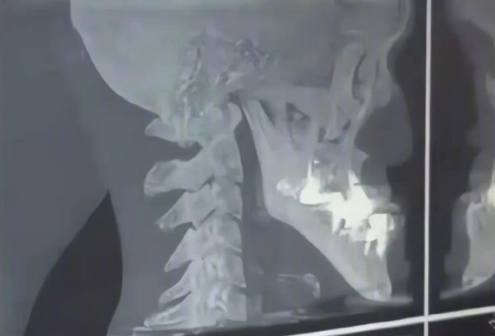

之后,医生又推断他是牛奶喝多了,导致下颌骨或牙龈过度增长并变异,并推荐他去牙科拍个X光试试。

结果显示,他的骨骼和牙齿都没问题,就是单纯的发育过长。

普通人下巴长度约为3厘米,而目前他以正面5厘米、侧面11.5厘米的下巴长度,成为目前有详细报道的自然发育最长下巴纪录保持者。